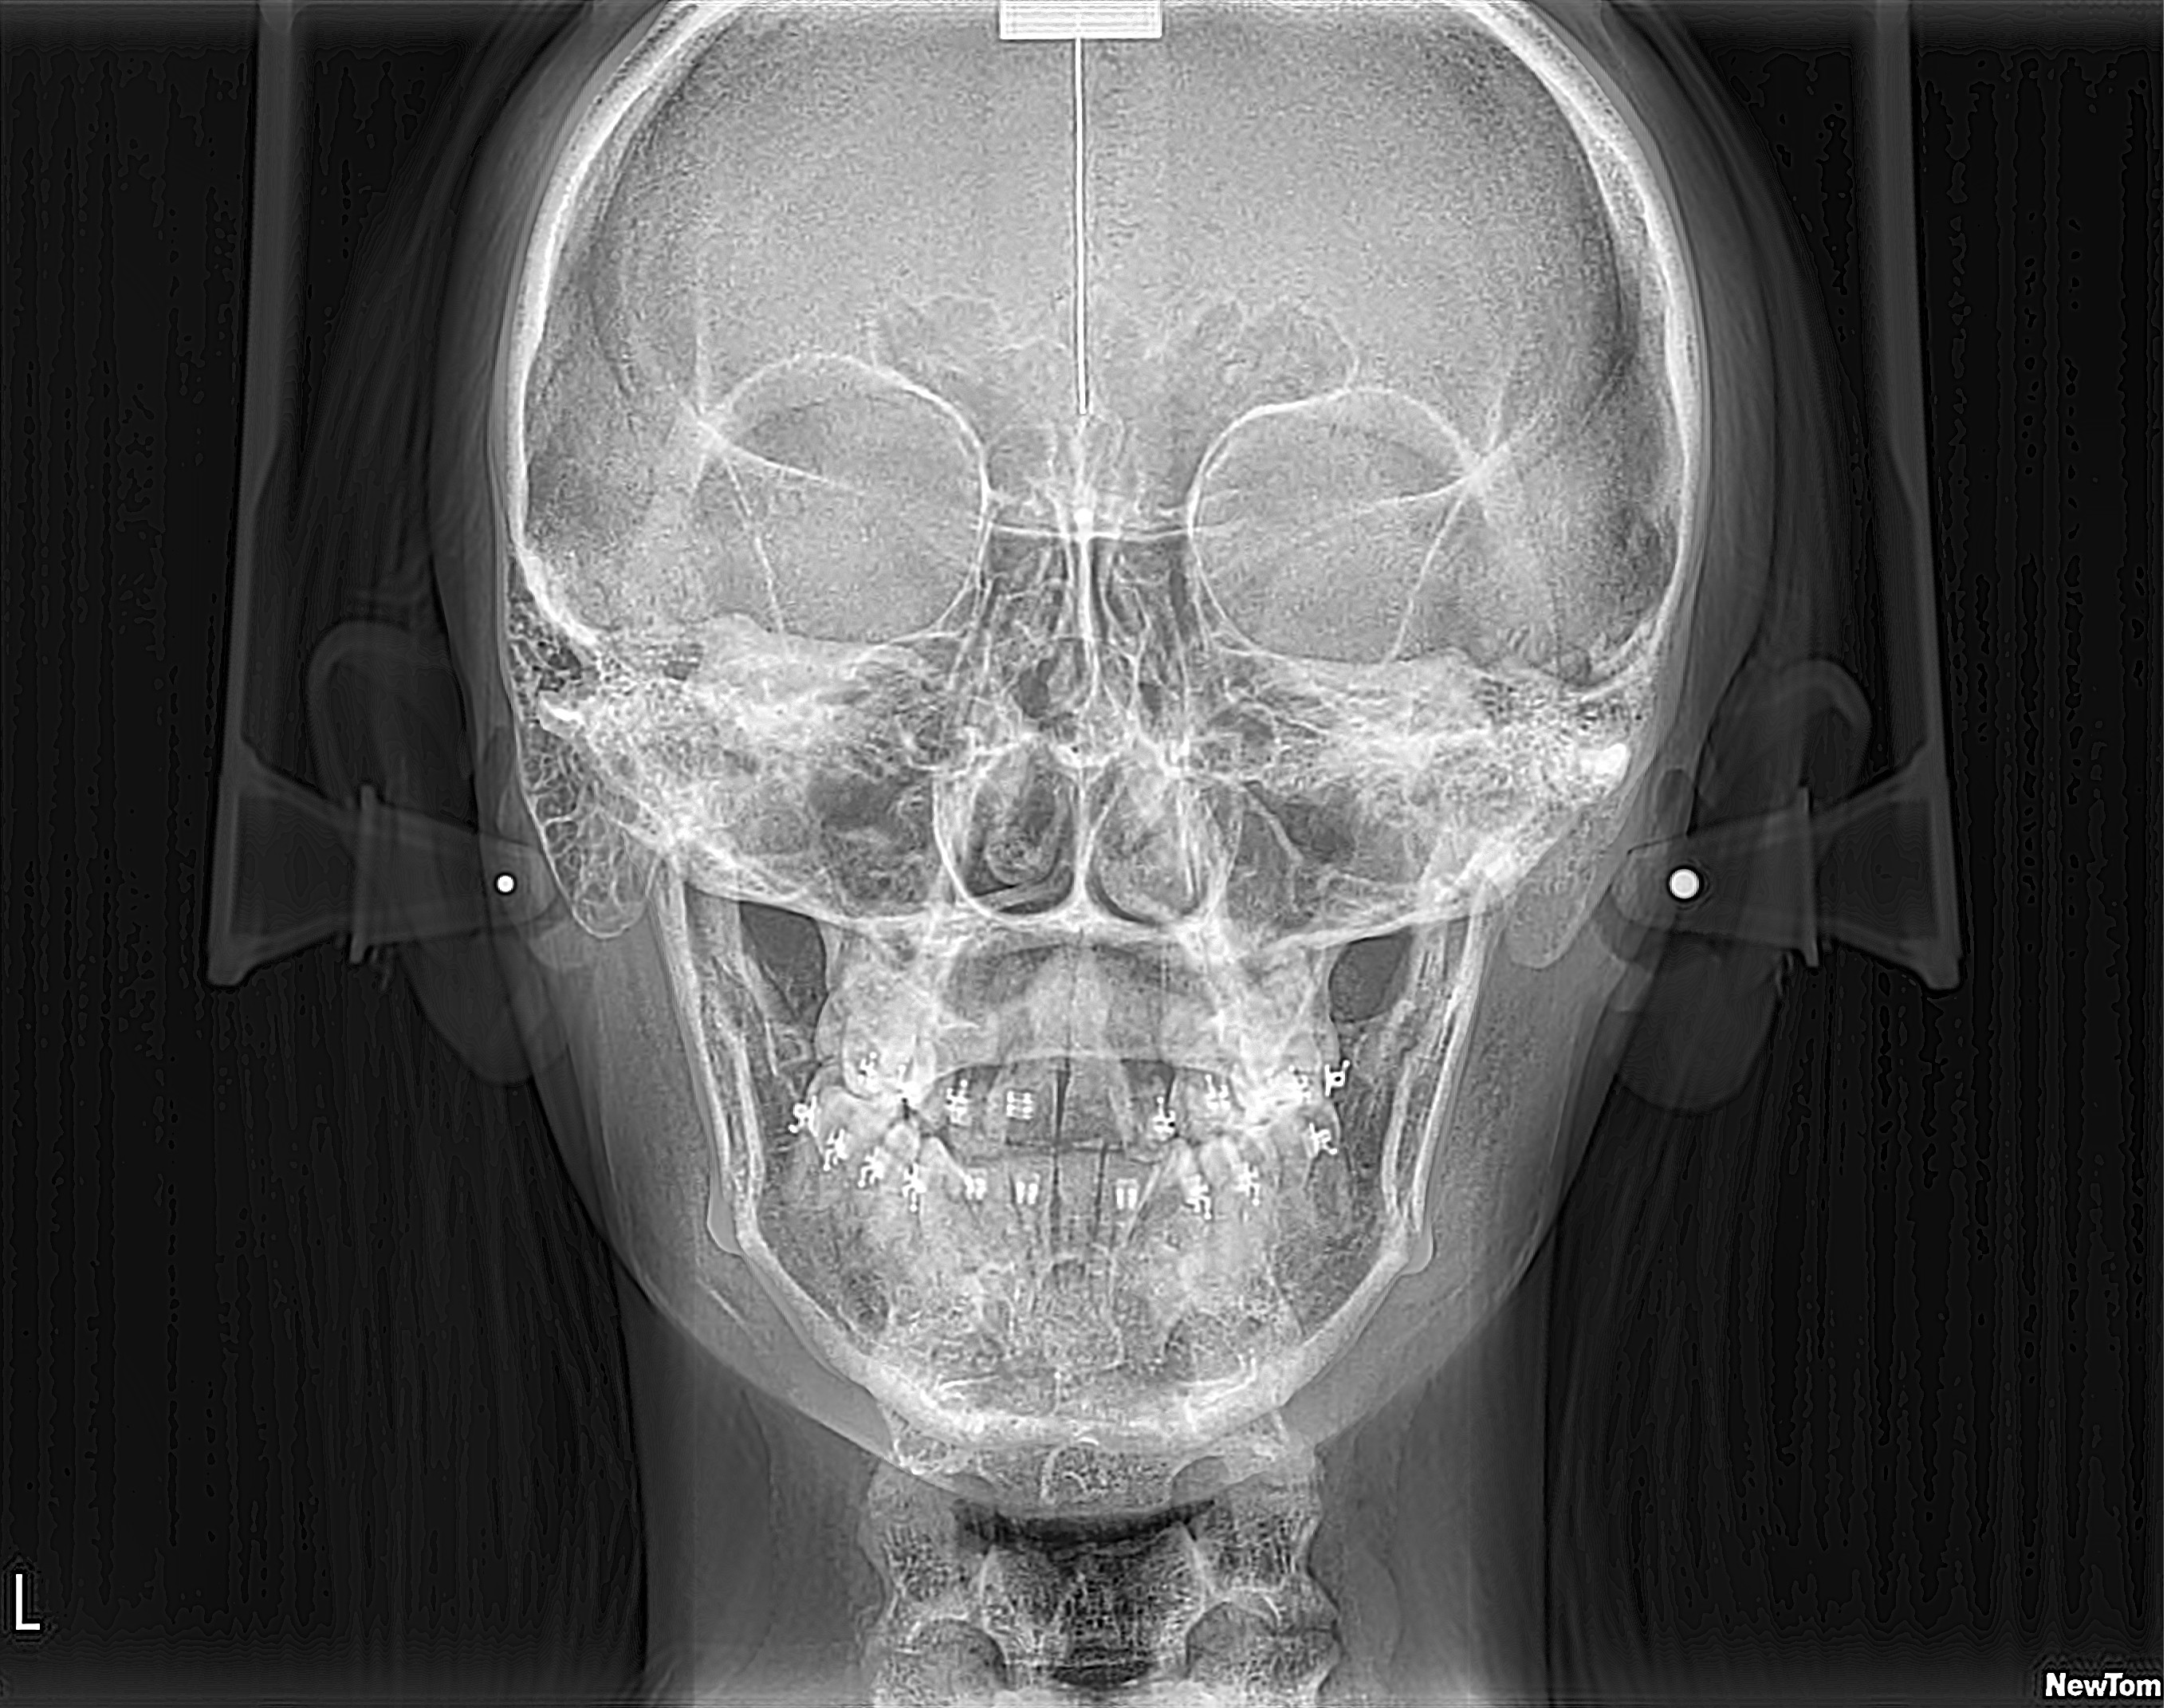

Telerradiografía Frontal

Evaluación profunda de asimetrías faciales. Vital para ortodoncia, cirugía maxilofacial y estudios de estructuras frontales.